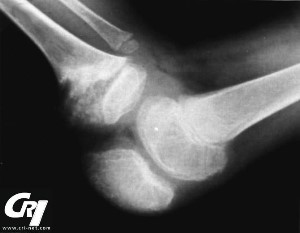

Joint & Orthopedic Symptoms

cri-net.com

Articular (joint) affects are present in variable degrees in most patients with NOMID/ CINCA. Periodic swelling without damage between flare-ups of inflammation are generally present. There can also be disfiguring and uncontrolled anomalous changes to the growth cartilage, often at the knees, suggestive of a pseudo-tumor growth. Many people that have developed this have enormously enlarged kneecaps (patellas) and other bony overgrowth at the large joints. This can occur in approximately 50% of people with NOMID. Often, biopsy findings show disorganized cartilage with no inflammatory cells present.

In the past, physicians thought that the enlarged, bony overgrowth was a necessary characteristic in order to diagnose someone with NOMID/CINCA, but now it is known that not all people with this syndrome develop the irreversible, disfiguring and debilitating damage to the joints. There is a great degree of variance in inflammation, deformity and pain in the joints with NOMID/CINCA.